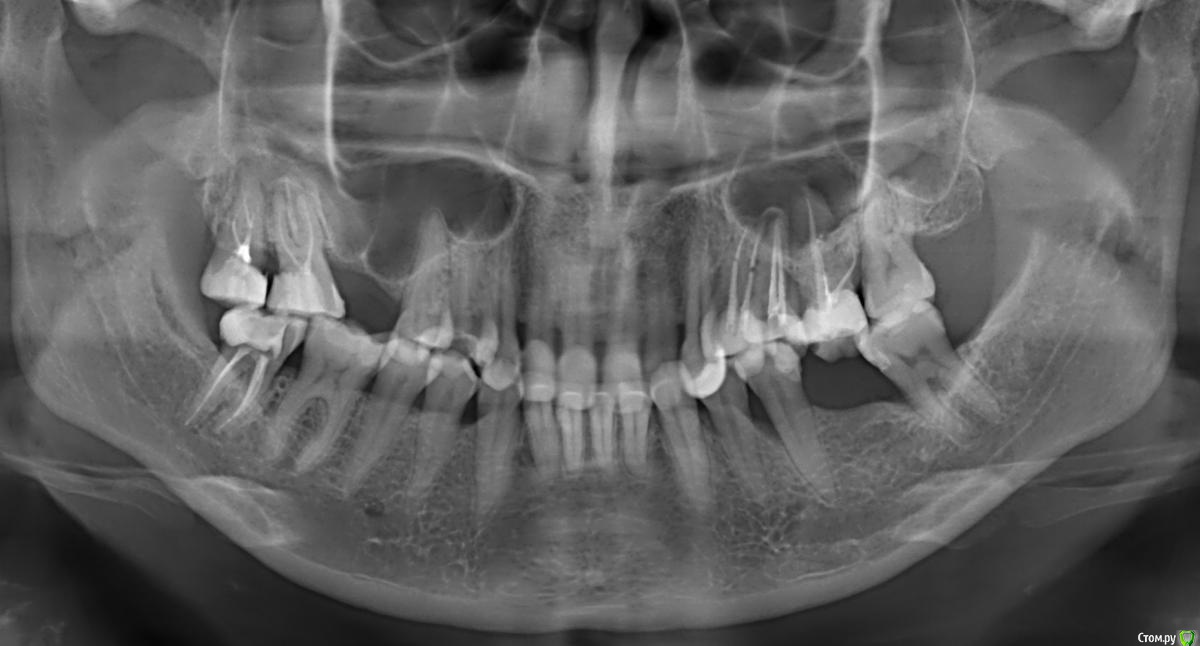

Нади999 Опубликовано 2 июня, 2015 Автор Поделиться Опубликовано 2 июня, 2015 Прикрепляю снимок. Ссылка на комментарий

Bier Опубликовано 2 июня, 2015 Поделиться Опубликовано 2 июня, 2015 проблем с синусом нет, но есть проблемы с соседними зубами. Рекомендации врача в личке. Ссылка на комментарий

red_butler Опубликовано 2 июня, 2015 Поделиться Опубликовано 2 июня, 2015 По этому снимку можно судить о костном предложении по высоте. На верхней челюсти требуется синуслифтинг, проблем тоже не вижу Ссылка на комментарий